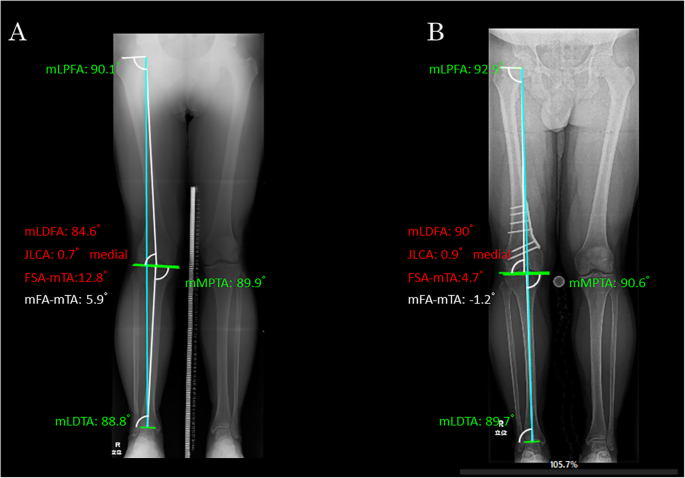

The alignment parameters were measured on the long-leg weight-bearing radiograph. The parameters subjected to the analysis were as follows: mechanical lateral distal femoral angle (mLDFA), mechanical medial proximal tibial angle (mMPTA) and mechanical tibiofemoral angle (mTFA). The radiological measurements were performed using digital planning software (mediCADR, Hectec, Germany) [13]. The assessments were performed before surgery as well as at 1 and 2 years after surgery. Subsequently, the measured values at each of the time periods were compared (Fig. 1).

Measurement of lower extremity alignment on the long-leg weight-bearing radiograph using the image analysis software (mediCADR). a Preoperative and (b) Postoperative. Blue line (mechanical axis). white line (mechanical femoral and tibial axis). FSA femoral shift axis, JLCA joint line conversion angle, mFA mechanical femoral angle, mLDFA mechanical lateral distal femoral angle, mLDTA mechanical lateral distal tibial angle, mLPFA mechanical lateral proximal femoral angle, mMPTA mechanical medial proximal tibial angle, mTA mechanical tibial axis

The intrarater reliability was shown to be excellent (intraclass correlation coefficient = 0.872). The pre- and postoperative radiological parameters measured for coronal alignment of the lower extremity were as follows: mLDFA, from 84.3 ± 2.0° to 89.3 ± 1.8° with significant postoperative increase (P < 0.001); mTFA, from 4.4 ± 4.7° valgus to 0.2 ± 4.7° varus with significant postoperative change (P < 0.001) (Table 2). The preoperative, 1-year postoperative and 2-year postoperative parameters related to the patellar height were as follows: 1.1 ± 0.2, 1.1 ± 0.2 and 1.1 ± 0.2 for mISI; 1.0 ± 0.2, 1.0 ± 0.2 and 0.9 ± 0.1 for mCDI; and 0.9 ± 0.2, 0.8 ± 0.2 and 0.8 ± 0.2 for mBPI, respectively (not significant). No significant changes over time were seen in all parameters (Table 3). The preoperative, 1-year postoperative and 2-year postoperative radiological parameters related to the patellofemoral alignment were 5.1 ± 3.9°, 4.6 ± 4.2° and 4.4 ± 4.4° for LPT, and 6.8 ± 3.4%, 6.8 ± 6.0% and 7.7 ± 4.4% for the LPS, respectively (not significant). Again, both parameters showed no significant changes over time (Table 4). When the LPT and LPS were examined for individual cases, 13 out of 21 cases were found to have decreased tilt after surgery, four cases had no change, and four cases had an increase in tilt. Nine out of 21 cases had a decrease in postoperative shift, two had no change, and 10 had an increase in shift.

Representative case of changes in total leg length and patellar congruity before and after surgery. a Preoperative in a 53-year-old female; the patient is presented with a valgus knee with mechanical lateral distal femoral angle (mLDFA) 82.5° and mechanical femoral angle (mFA)-mechanical tibial angle (mTA) 14.6°. Lateral patellar tilt (LPT) was 4.0° and lateral patellar shift (LPS) was 7.8%. b Postoperative; the mLDFA and mFA-mTA changed to 91.9° and -2.1°, respectively. LPT remained unchanged at 4.0° and the LPS was 11.1%. FSA femoral shift axis, JLCA joint line conversion angle, mLDTA mechanical lateral distal tibial angle, mLPFA mechanical lateral proximal femoral angle, mMPTA mechanical medial proximal tibial angle